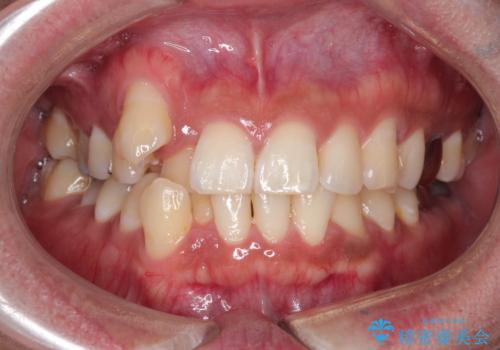

【ワイヤー矯正】八重歯と下の歯の凸凹を治したい

- 主訴:右上の八重歯と、下の歯の凸凹を治したい

右側2級、左側1関係だったため、右側上下第一小臼歯を抜歯し、ワイヤー矯正を行いました。